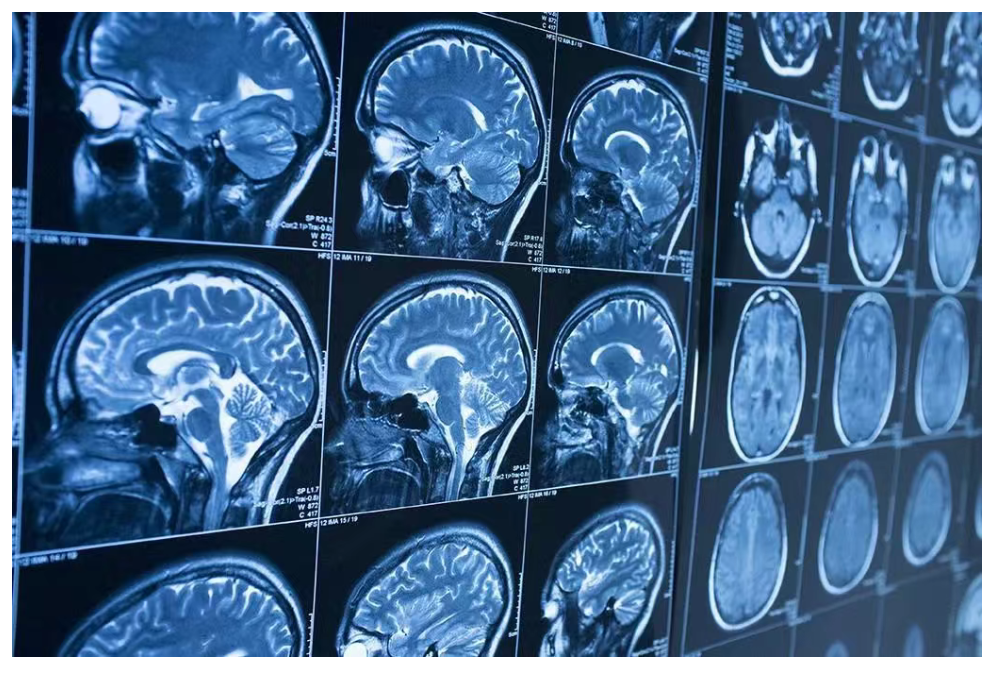

阿尔茨海默症目前是根据PET扫描或脑脊液分析的结果诊断的,但是与这两个金标准相比,血液检测的侵入性更小、成本更低,因此在诊断和管理阿尔茨海默症方面发挥重要作用。与此同时,生物标记物的发现和检测的进步使检测患者血液中与阿尔茨海默症相关的分析物成为可能,提高了诊断的可能性,从而可以在大规模、潜在无症状的人群中低成本和大规模地进行。